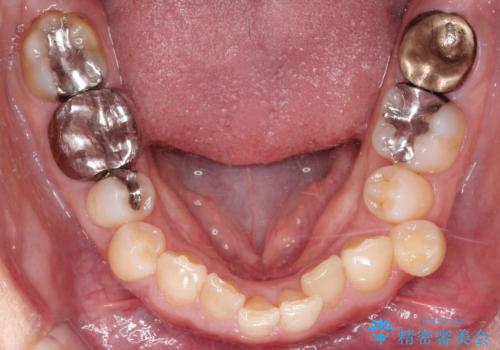

【インビザライン】重度叢生をなおしたい

- 全体的に歯並びをなおしたいことを主訴に来院されました。

上顎前歯が舌側傾斜していたため少し拡大を行いながら非抜歯で治療を行っています。

マウスピースをしっかり使用していただいたので、きれいな歯並びになりました。